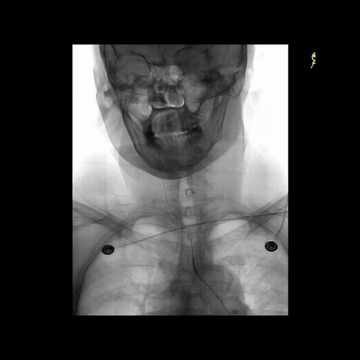

CTA:弓上血管迂曲,右侧颈内动脉行程迂曲,其远端闭塞。

CTA:右侧颈内动脉末端分叉部T栓塞。

5F多功能管(125cm)+6F长鞘(90cm,Cook)组成同轴,泥鳅导丝导引下,快速过弓,把长鞘头端送至右侧颈总动脉远端,造影见溶栓后栓子迁移至M1远端;泥鳅导丝导引5F中间管克服C1段迂曲,上高到海绵窦段,同时尽量上高长鞘增强支撑。